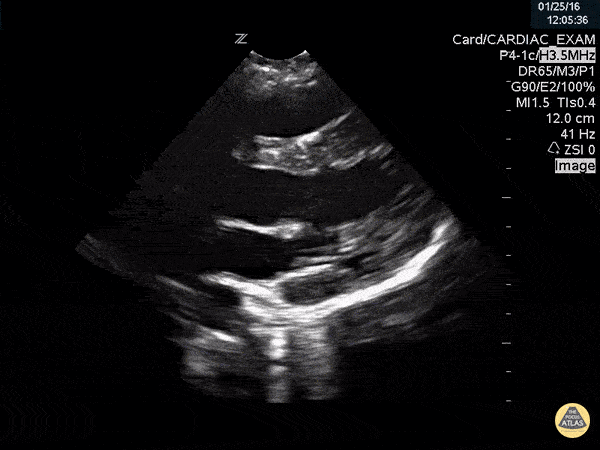

Thoracic Aortic Dissection & Aneurysm - Aortic Dissection Flap Visualized in Proximal Aorta with Root Dilation

This is a parasternal long axis view demonstrating significant enlargement of the aortic root with an identified dissection flap located in the proximal ascending aorta. Frances Russell, MD, RDMS Assistant Professor of Emergency Medicine Division Chief, Ultrasound Fellowship Director, Ultrasound